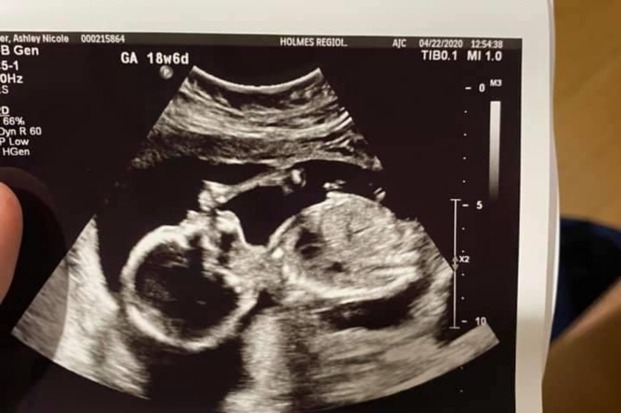

On Saturday, July 4th, we lost one of our own. Steven Livingston, a loving father, partner and son left this earth too soon. His friends and family at Health First want to support Ashley and Baby Livingston and have started this fund in his name. Thank you for blessing us during your time here Steven. We will miss you. Ashley-we are here for you and Baby Boy!